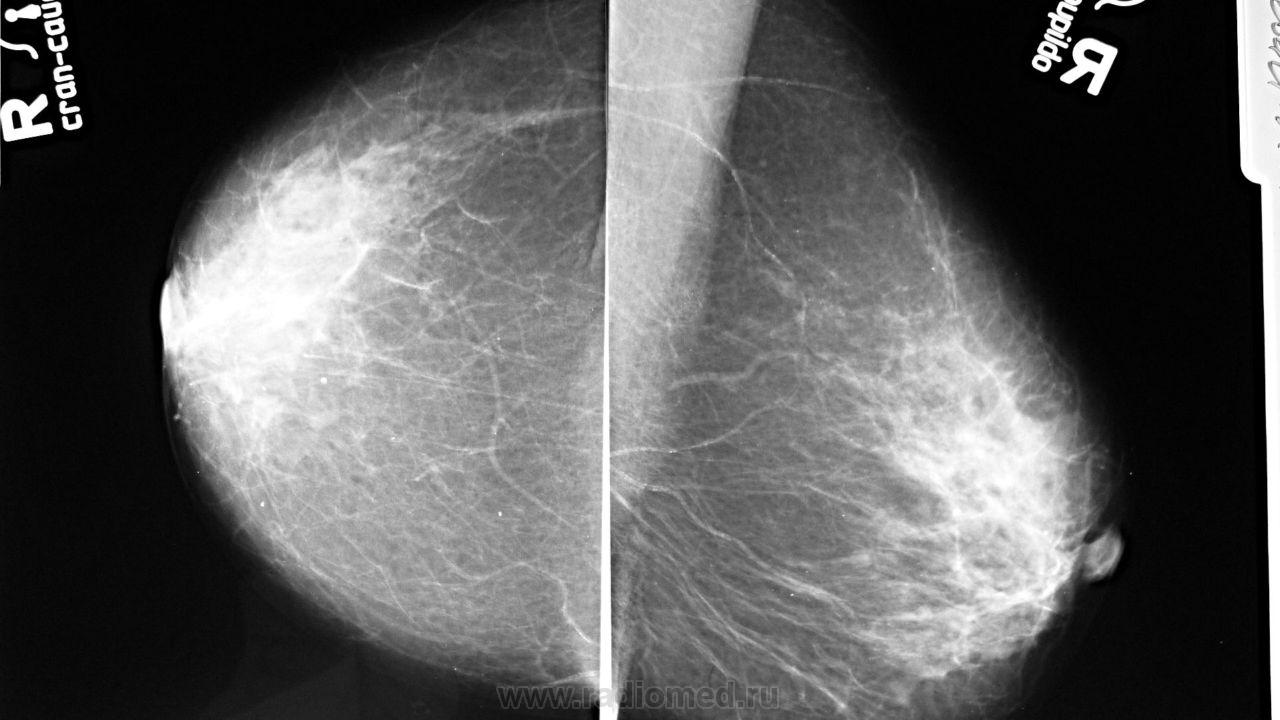

Ваше мнение о левой железе?

Я еще только учусь, не ругайте, пожалуйста. В нижне-внутреннем квадранте это обызвествленный кровеносный сосуд? И в верхне-наружном объемное неоднородное образование с нечеткими контурами (спикулами)? А в центре его, при увеличении,плотность выше, можно ли думать о микрокальцинатах, или это плохо видно? Есть ли возможность выполнить цветное допплеровское картирование?

Вот-вот именно верхне-наружный мне и не понравился и за счет своей неоднородности..

suspicio neo в в/н квадранте левой молочной железы - консультация онколога